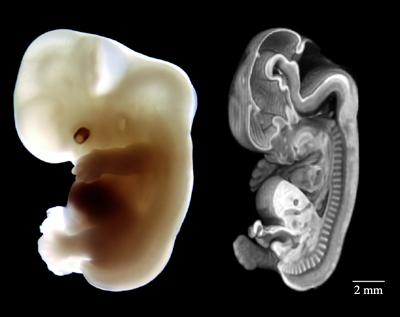

50-Day Human Embryo

Photo-micrograph and MRI of same embryo.